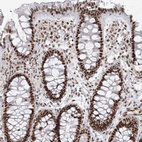

Immunohistochemical staining of human testis shows strong nuclear positivity in cells in seminiferous ducts.